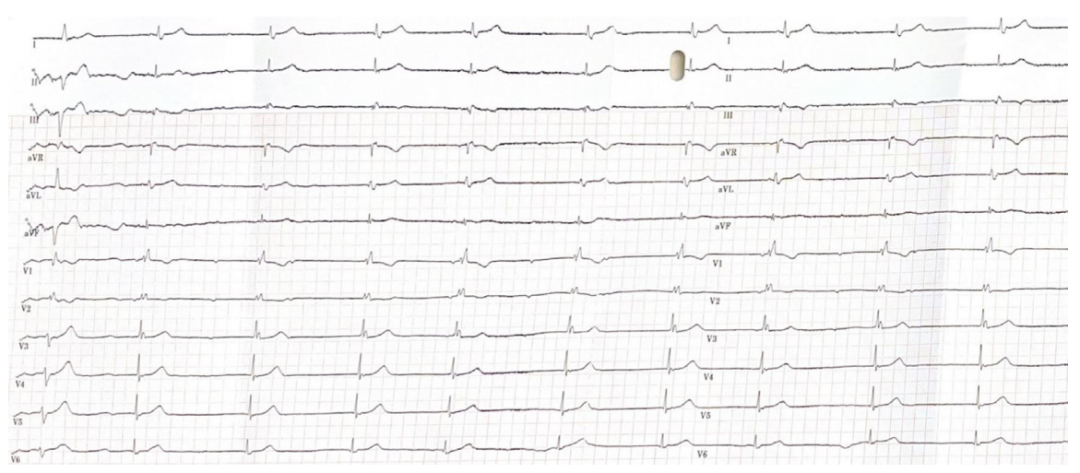

56岁女性,CABG术后出现疲劳、胸痛,心电图你怎么看?

病史摘要:56岁女性,因三支冠脉病变行冠状动脉旁路移植术(CABG)。术后常规随访时,出现疲劳、胸痛(与胸骨切口无关且非心绞痛)、呼吸困难及外周水肿症状。诊疗过程:体格检查、超声心动图与12导联心电图检查结果一致。心电图显示心律规则,心率130次/分钟,为窦性心动过速伴电交替,电轴右偏。结合病史,考虑左后分支传导阻滞,QRS波振幅逐搏变化提示大量心包积液或心包填塞,aVR导联P波电

起博心律患者出现胸痛应紧急再灌注?你如何判读

病史摘要:74岁男性,有非缺血性心肌病病史及双心室起搏器植入史。因间歇性胸痛2天,持续4小时,伴大汗、呼吸短促至急诊科就诊。诊疗过程:患者生命体征正常,12导联心电图显示心房感知双室起搏伴室性早搏,符合起搏心律下的Aslanger模式,提示下壁闭塞性心肌梗死。两小时后出现多形性室性心动过速。首次高敏肌钙蛋白I显著升高,被诊断为非STEMI,入院至置管时间20小时。血管造影显示右冠状